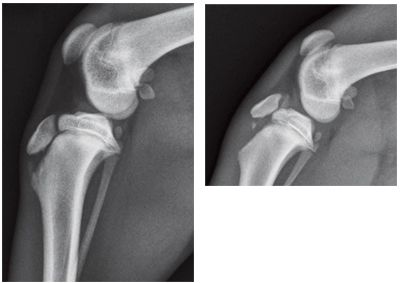

Radiographic interpretation is a learned skill. Interpretation errors can be divided into two categories. There are errors of omission and errors of interpretation.

Normal and abnormal radiographs of a variety of conditions in the pet rabbit will be presented.

Disease processes are categorized into Congenital, Degenerative, Developmental Inflammatory, Metabolic, Neoplastic, Traumatic and Miscellaneous processes.

Disease processes are categorized into Congenital, Degenerative, Developmental, Inflammatory, Metabolic, Neoplastic, Traumatic and Miscellaneous processes.